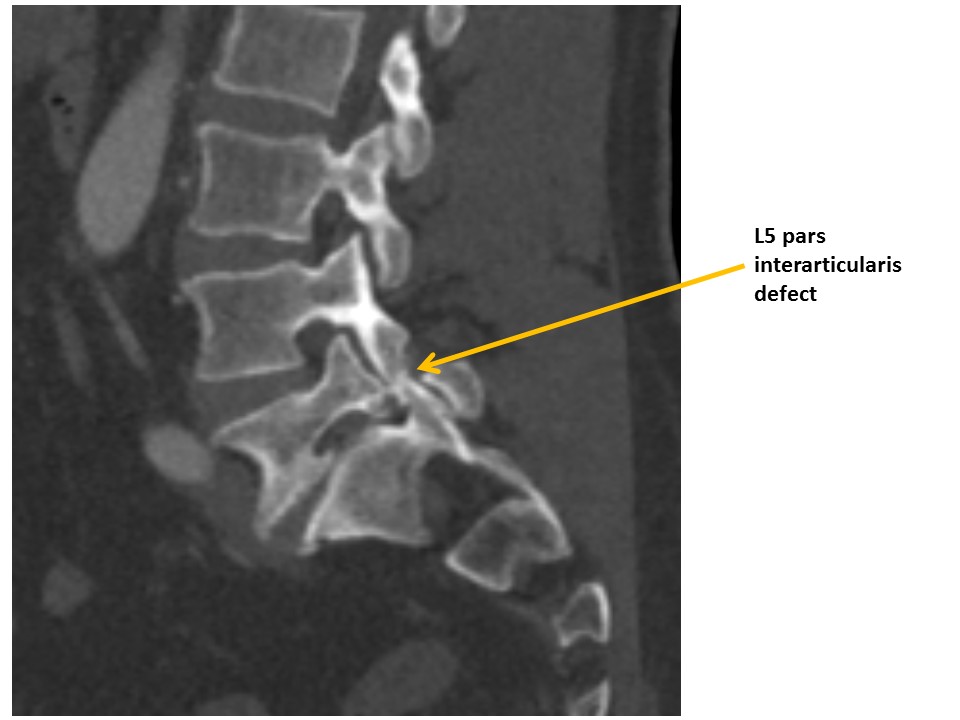

VISUALIZED LUMBAR SPINE

There are compression fractures, transverse process fractures, or malalignment. [Yes/No]

There are pars interarticularis defects. [Yes/No]

There are degenerated discs or facet osteoarthritis. [Yes/No]